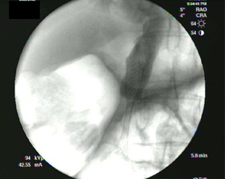

Photo of stint from endoscopic camera

A stent placed in the colon